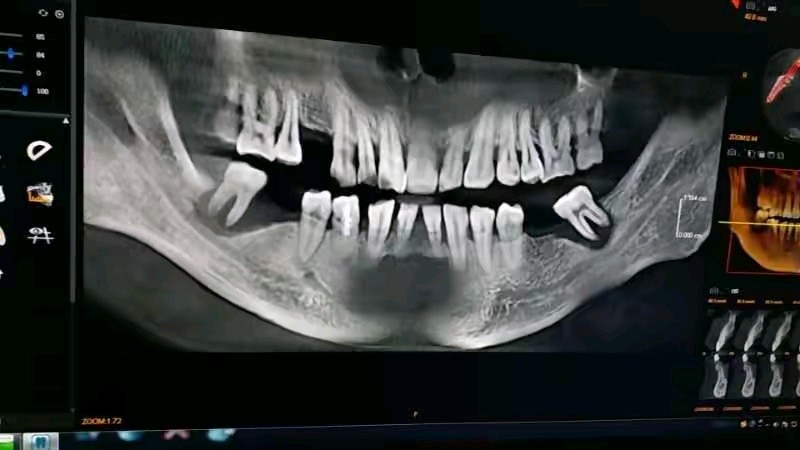

看到我磨牙的方向了吧!就是这样,长驱直入到舌侧,整个分两段吧

不过有时候不如人愿,看不到漂亮的线啦,因为实在是空间狭小,只能让他先出来一点,近点灯光啦。最后,就碎喽。

幸好,都是单根,那想这样两个根卡抱着,你就在那里好好晃吧,晃到牙槽间隔挤压变形,最后才能出来。